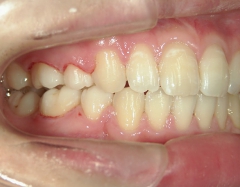

矯正歯科(全顎ワイヤー矯正)治療後

治療期間2年4

ヶ月

矯正歯科 治療後